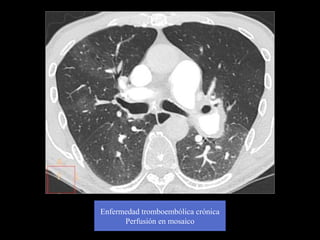

Enfermedad tromboembólica crónica

Perfusión en mosaico